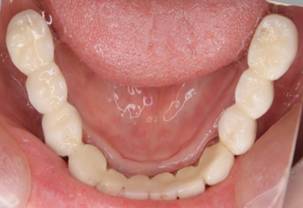

下顎

術後。上部構造はハイブリッドレジンです。しっかり嚙めるようになり喜んでいただきました。

下顎。12か月に一度メインテナンスをしています。

インプラント装着後6年。順調に経過しています。12か月毎のメインテナンスをしています。